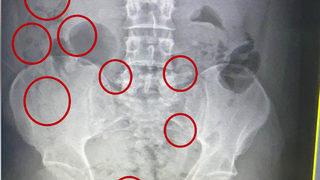

Röntgen haberleri sayfası, sağlık sektöründeki en son gelişmeleri takip etmek isteyenler için önemli bir kaynak sunmaktadır. Günümüzde tıbbın vazgeçilmez bir parçası haline gelen röntgen teknolojisi, hastalıkların teşhisinde ve tedavisinde kritik bir rol oynamaktadır. Bu sayfa aracılığıyla, günlük yaşamını etkileyen son dakika röntgen gelişmelerine erişebilir, güncel röntgen haberlerini takip edebilir ve ilgili konularda bilgi sahibi olabilirsiniz.

Sağlık alanında meydana gelen yenilikler ve röntgen uygulamalarındaki ilerlemeler, hastaların diagnostik süreçlerini dönüştürmektedir. Özellikle son dakika röntgen haberleri, bu alandaki en güncel ve önemli bilgileri içermekte; okuyuculara profesyonel ve akademik perspektifler sunmaktadır. Röntgen haberleri sayfamızda, uzman görüşleri ve araştırmalara dayanan içeriklerle sağlık alanındaki gelişmeleri yakından takip edebilirsiniz.